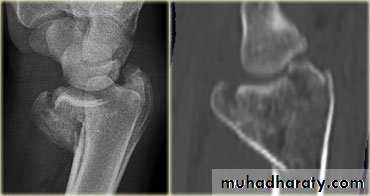

Scaphoid fractures:Its account for almost 75% of all carpal fractures, its rare in the elderly and children.

Mechanism of fracture: fall on dorsiflexed hand.

X-ray : AP, Lateral and oblique views.

Avascular necrosis: the proximal fragment may die, especially with proximal pole fracture. It appears dense on X-ray after 2-3 months.Non-union: if the fracture is not united after 3 months.